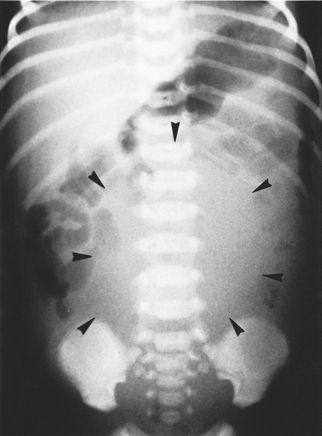

Blockage

A baby born in Saskatchewan was circumcised with

a Plastibell

TM at six

days old. In the next two days his bladder swelled

to the size of a tennis ball (in a newborn, that's

big). This put pressure on his inferior vena cava,

the main vein draining the lower body, which

caused his lower body to swell and turn blue.

Click

on

the thumbnail for a full-size image

Going in through the baby's belly, doctors

drained 200 mL of urine. When they removed the

Plastibell TM,

they found it was embedded in his glans.

The baby passed more than 600 mL of urine in the

following 12 hours. It took him two days to

recover.

One study of 2000 PlastibellTM

circumcisions found a complication rate of 1.8%.

- Linh Ly and Koravangattu Sankaran

Acute

venous

stasis

and swelling of the lower abdomen

and extremities in an infant

after circumcision

CMAJ 2003; 169: 216-217